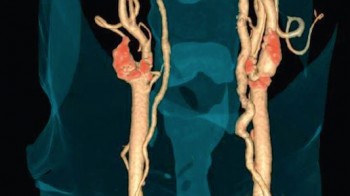

CT-kolonografija

Karcinom kolona (debelog crijeva) je drugi po učestalosti međju karcinomima kod muškaraca (iza karcinoma pluća) te treći po učestalosti kod žena (iza karcinoma dojke i cerviksa) i najsigurniji nacin rane detekcije jeste uraditi kolonoskopiju. Osim klasične endoskopske metode, danas imamo na raspolaganju i mogućnost CT kolonoskopije, koja je puno jednostavnija i za pacijenta komfornija, a po rezultatima nalaza komparabilna s klasičnom kolonoskopijom. U 22 američke savezne države kolonoskopija je pregled koji ide na teret fonda zdravstvenog osiguranja.

Šta je CT kolonografija?

CT kolonografija ili virtualna kolonoskopija je procedura koja koristi viseslojni CT za pregled debelog crijeva na prisustvo karcinoma ili prekanceroznih polipa. Njome se mogu otkriti tumori, polipi, krvarenje, upalne bolesti crijeva te divertikuloza.